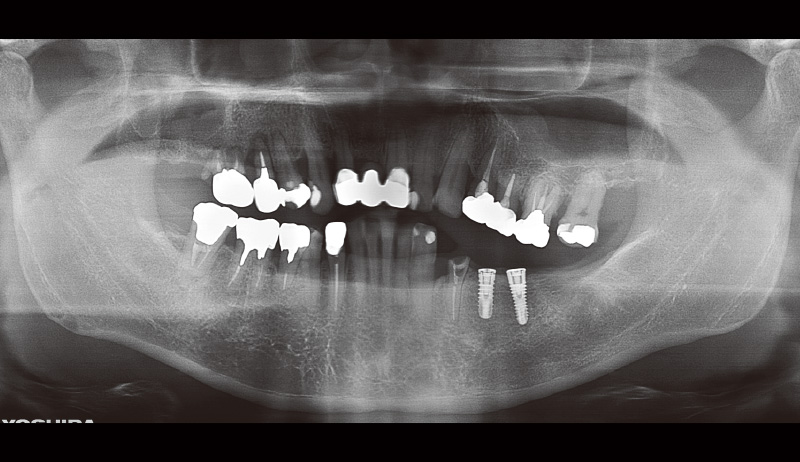

51歳男性、主訴:左下の奥歯で噛めるようになりたい(図14, 15)。

この症例が私にとって初めてのSPIインプラント症例だった。ドリルキットがとても簡便で操作性も良く感じた。こちらの症例は初心者でもできる症例を挙げているので参考にしていただけたらと思う(図16~19)。

まずフラップを開く前にヨード染色を行い、付着歯肉の幅を確認する。その後、フラップを全層弁で開く(私の場合はそこまで大きくは開けないことが多い)。床形成を行い平行指示ピンを入れ平行性を確認。SPIイニセルインプラントをコンディショニングした状態で埋入の準備を行う。₅:φ4.0長さ11mm、 ₆:φ4.5長さ11mmのSPIイニセルインプラント エレメントRCを埋入。付着歯肉を減らさないように縫合を行った。

![[写真] 初診時のパノラマX線写真](/academic/dentalmagazine/wp-content/uploads/sites/2/2025/09/194-8_photo15.jpg)

図15 初診時のパノラマX線写真 -

![[写真] インプラント埋入後のパノラマX線写真](/academic/dentalmagazine/wp-content/uploads/sites/2/2025/09/194-8_photo17.jpg)

図17 インプラント埋入後のパノラマX線写真(₅のヒーリングキャップが甘く締められていることを確認したので再度締め直しを行った)。 -

![[写真] 完成後のパノラマX線写真](/academic/dentalmagazine/wp-content/uploads/sites/2/2025/09/194-8_photo18.jpg)

図18 完成後のパノラマX線写真 -